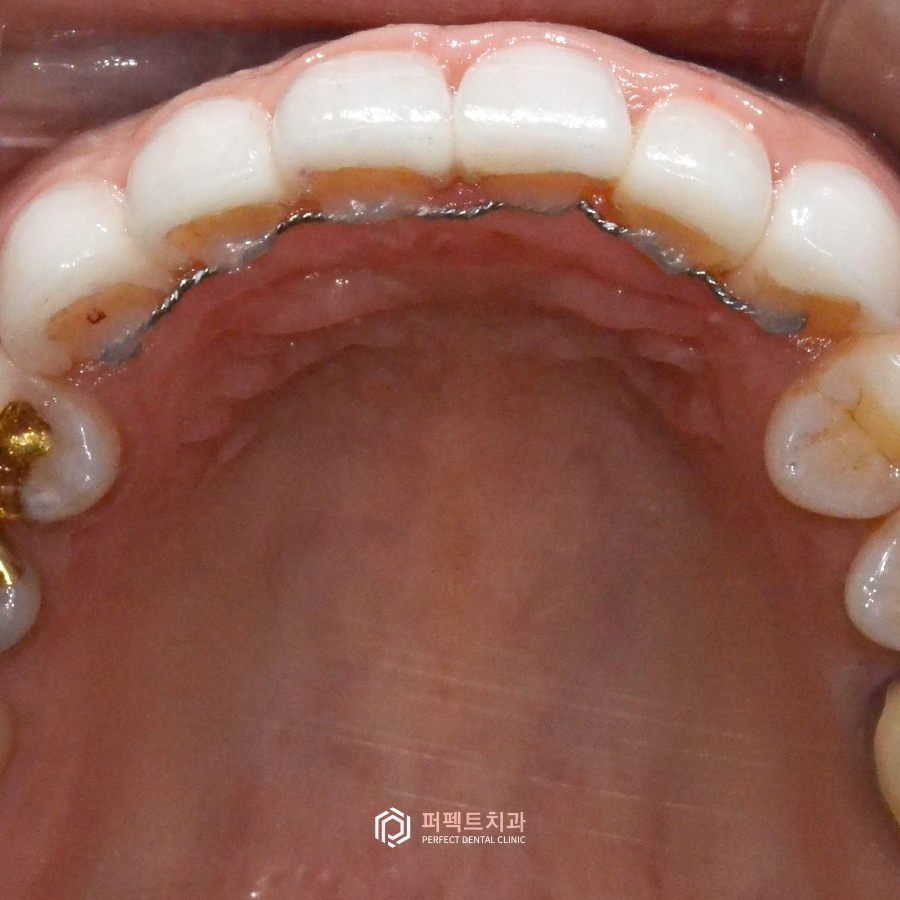

이 유지장치도 여러 종류가 있습니다. 첫 번째로 고정성 유지장치란 치아 배열이 유지될 수 있도록 치아 뒷면에 철사로 고정 시키는 장치이며, 두 번째로 가철성 유지장치는 자유롭게 꼈다, 뺐다 할 수 있는 장치입니다.

그런데 여기서 생각해보아야 할 부분은 라미네이트는 치아의 앞면에만 보철을 부착하기 때문에 뒤에 고정성 유지장치가 잘 붙어있지만 올세라믹이나 지르코니아 크라운 같은 크라운치료를 했다면 세라믹or지르코니아 재질이기 때문에 철사가 잘 떨어지는 경향이 있어 이러한 부분에 주의를 해주어야 합니다.